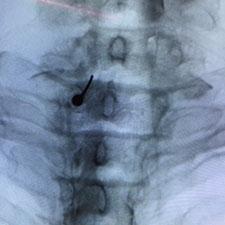

La figura muestra la aguja en el ganglio dorsal de la raíz de L5 izquierda, y el contraste inferior dibuja la raíz de S1 izquierda.